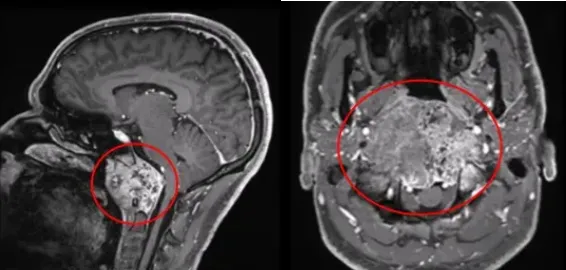

杰森因颈椎疼痛、吞咽困难、舌头发麻而查出一个巨大的颅颈交界区脊索瘤。肿瘤最大直径有10cm,体积达96.5cm³,简直是驻扎在他脑中的绿巨人。问遍各大医院,可有把握的医生寥寥,杰森的手术被一次次“婉拒”。

“唉,怪就怪这个肿瘤太聪明,长在颅颈交界这个十分难搞的位置。”医生摇头惋惜:“现在肿瘤体积巨大,不仅对脑干和双侧椎动脉产生压迫,还沿着硬膜内扩张,一路侵犯斜坡-枕髁区域,并且还有溶骨性破坏特征,手术风险太大了,很可能术后你就会肢体瘫痪。实在是手术难度太高,你再去别的医院问问吧……”

杰森的手术如期进行。福教授考虑到肿瘤已导致颅颈交界区骨质结构的广泛破坏和侵蚀,因此,他选择了远外侧经髁入路,通过显微镜和神经内镜的“双镜联合”技术切除肿瘤。